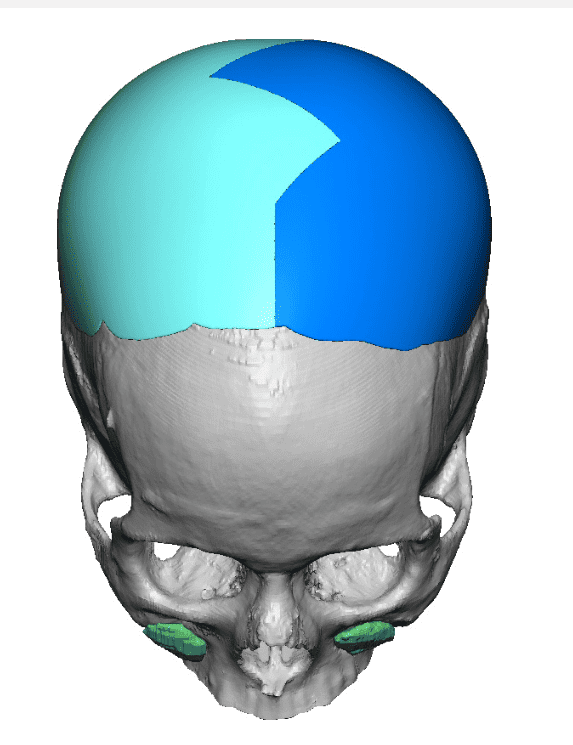

Patient 110

Desire for head shape asymmetry improvement as the final stage of total skull reshaping surgeries. (previous skull implants are in green color)

Placement of custom temporal implant through an incision behind the ear.

Desire for head shape asymmetry improvement as the final stage of total skull reshaping surgeries. (previous skull implants are in green color)

Placement of custom temporal implant through an incision behind the ear.